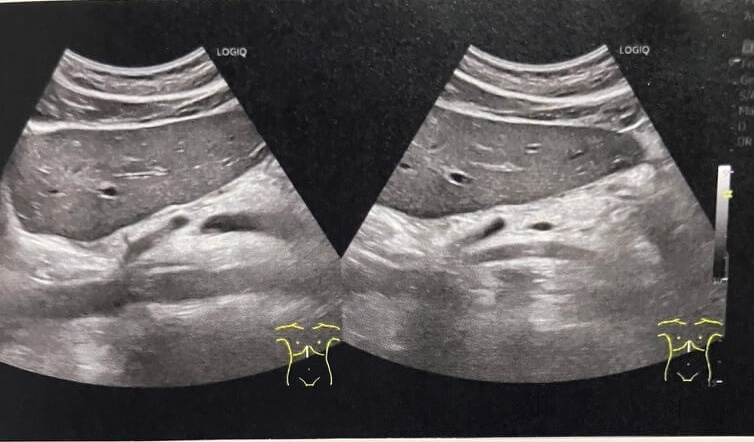

Bridging Vascular Sign

【腹部エコー】症例9 憩室炎

【腹部エコー】症例8 肝臓の辺縁鈍化とS1腫大

【腹部エコー】症例7 門脈圧亢進?

【腹部エコー】症例6 胆嚢腺筋腫症と急性胆嚢炎?